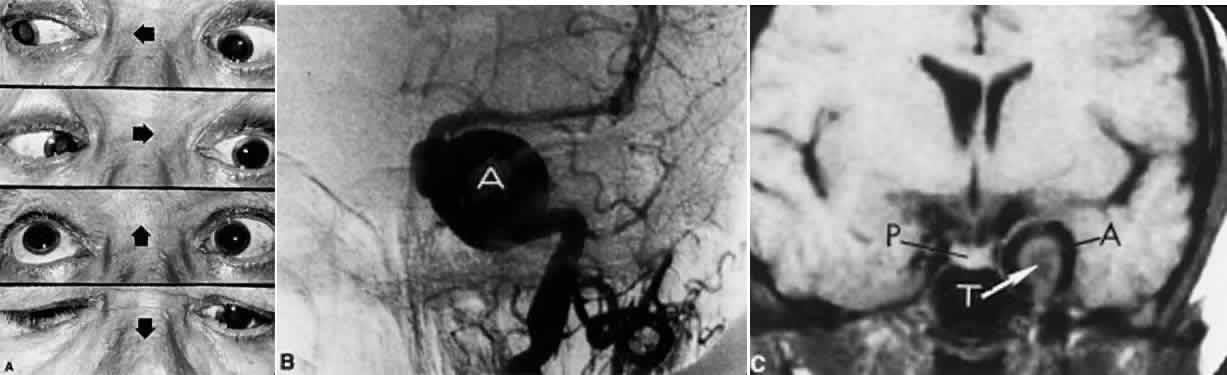

In the cavernous sinus, the abducens nerve may be involved in combination with the ophthalmic-trigeminal, third, or fourth nerves. Abducens monoparesis is frequent with cavernous sinus lesions, perhaps related to the nerve's location within the sinus, inferolateral to the carotid artery and unsupported by the dural wall of the sinus.19,20 Isolated abducens palsy occurs with carotid-cavernous fistulas (especially with spontaneous dural shunts21) and intracavernous aneurysms20 (Fig. 7), and is the earliest indication of contralateral spread of cavernous sinus thrombosis. Sixth nerve palsy accompanied only by ipsilateral Horner's syndrome also points to the cavernous sinus, since the ocular sympathetics from the carotid plexus may be simultaneously involved.22

Fig. 7. A. Chronic isolated sixth nerve palsy. B. Coronal and Axial (C) MRI sections showing large intracavernous internal carotid aneurysm (arrows).